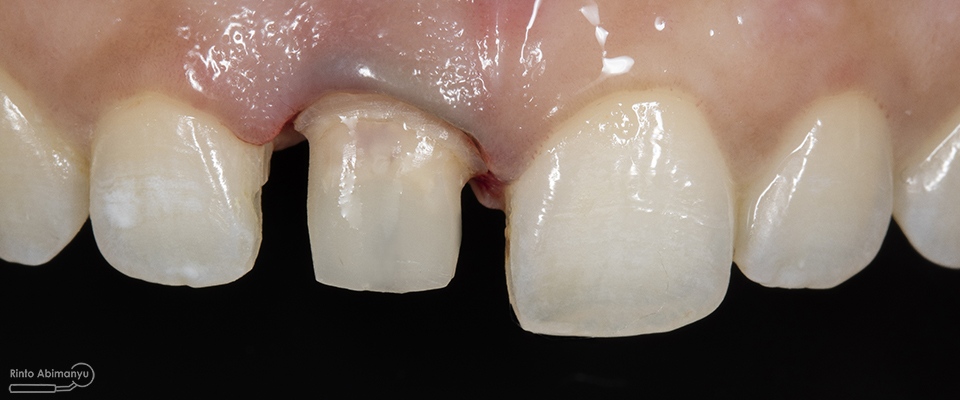

Begini kondisi klinis saat datang…

Foto klinis gigi-gigi anterior yang mengalami fraktur